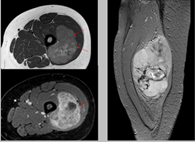

Se usa una amplia gama de técnicas de adquisición de imágenes para poder ver dentro del cuerpo y determinar el alcance de un sarcoma óseo y establecer la presencia o ausencia de enfermedad metastásica distante.

2. Resonancia magnética

3. TAC contrastado

Pruebas de imágen

Las pruebas de diagnóstico por imágenes utilizan ondas sonoras, rayos X, campos magnéticos o sustancias radiactivas para crear imágenes del interior del cuerpo. Las pruebas de diagnóstico por imágenes pueden realizarse por diversos motivos, como:

Las imágenes más representativas o más comunes son:

3. Tomografía Computarizada

5. Resonancia Magnética